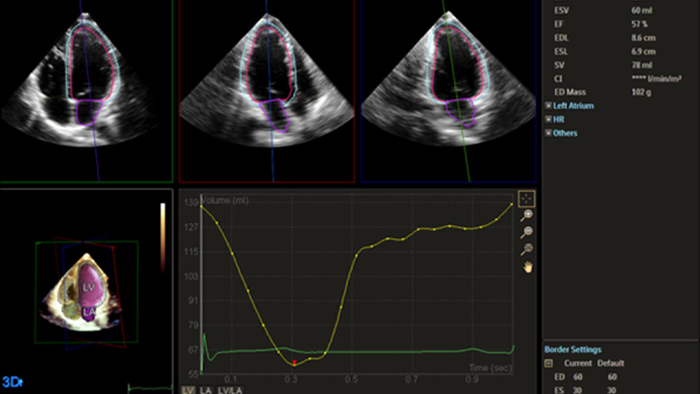

Heart failure is prevalent worldwide, and accurate assessment of heart function using echocardiography is essential.1,2 Incorporating strain and 3D assessment of the LV and RV has historically been challenging and required specialized skill sets.

Solution Philips IntelliSpace Cardiovascular multimodality image and information management solution offers a complete look at a patient’s cardiac history. The AI-enabled automation of Philips EPIQ CVx cardiovascular ultrasound system and Philips TOMTEC -ARENA quantification tools provides efficiency and reproducibility during echocardiography studies.

Philips solutions allow for advanced quantification and analysis, with access to information anywhere, anytime across the enterprise. AI-enabled, automated tools for visualization, analysis and streamlined reporting offer robust, reproducible results to help make the effective management of heart failure a reality.

Echo is often the first cardiac imaging test that’s performed for patients with suspected heart failure. An echocardiogram gives us a wealth of information on cardiac structure and function using both 2D and 3D tools. Echocardiography can help us understand the etiology of heart failure in many situations. I routinely use information derived from both 2D and 3D analysis and strain to better understand my patients. AutoStrain, Dynamic HeartModel and Auto RV are invaluable tools that are used both in the diagnosis and surveillance of patients with heart failure.”

Robust and reproducible imaging tools are important to diagnose and monitor disease progression in heart failure. Current guidelines support the use of advanced echocardiography tools such as longitudinal strain and 3D assessment of LV and RV volumes and function.

Automation for robust, proven reproducible cardiac quantification in both 2D and 3D.

Quantification through Dynamic HeartModel.